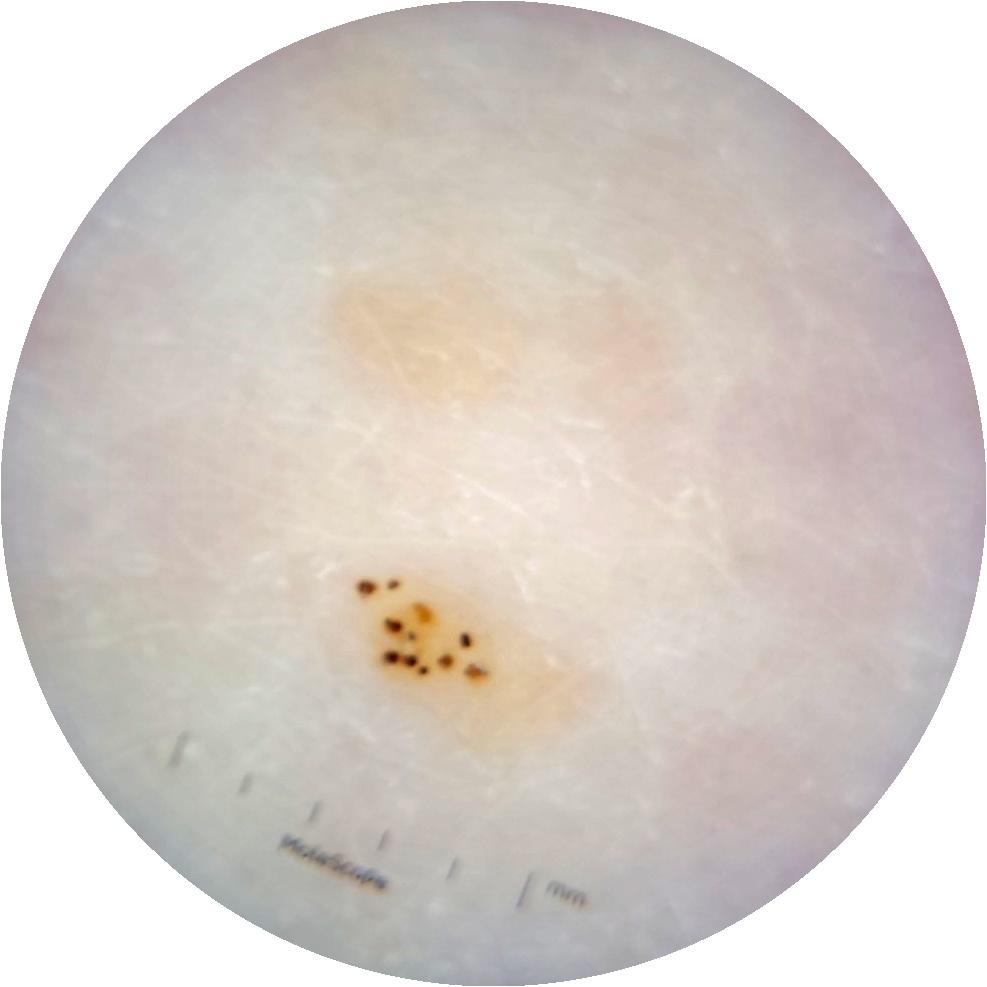

Clinical

Field Value

acquisition_day 264

age_approx 65

anatom_site_1 Trunk

anatom_site_2 Anterior trunk

anatom_site_general anterior torso

diagnosis_1 Benign

diagnosis_confirm_type single image expert consensus

image_type dermoscopic